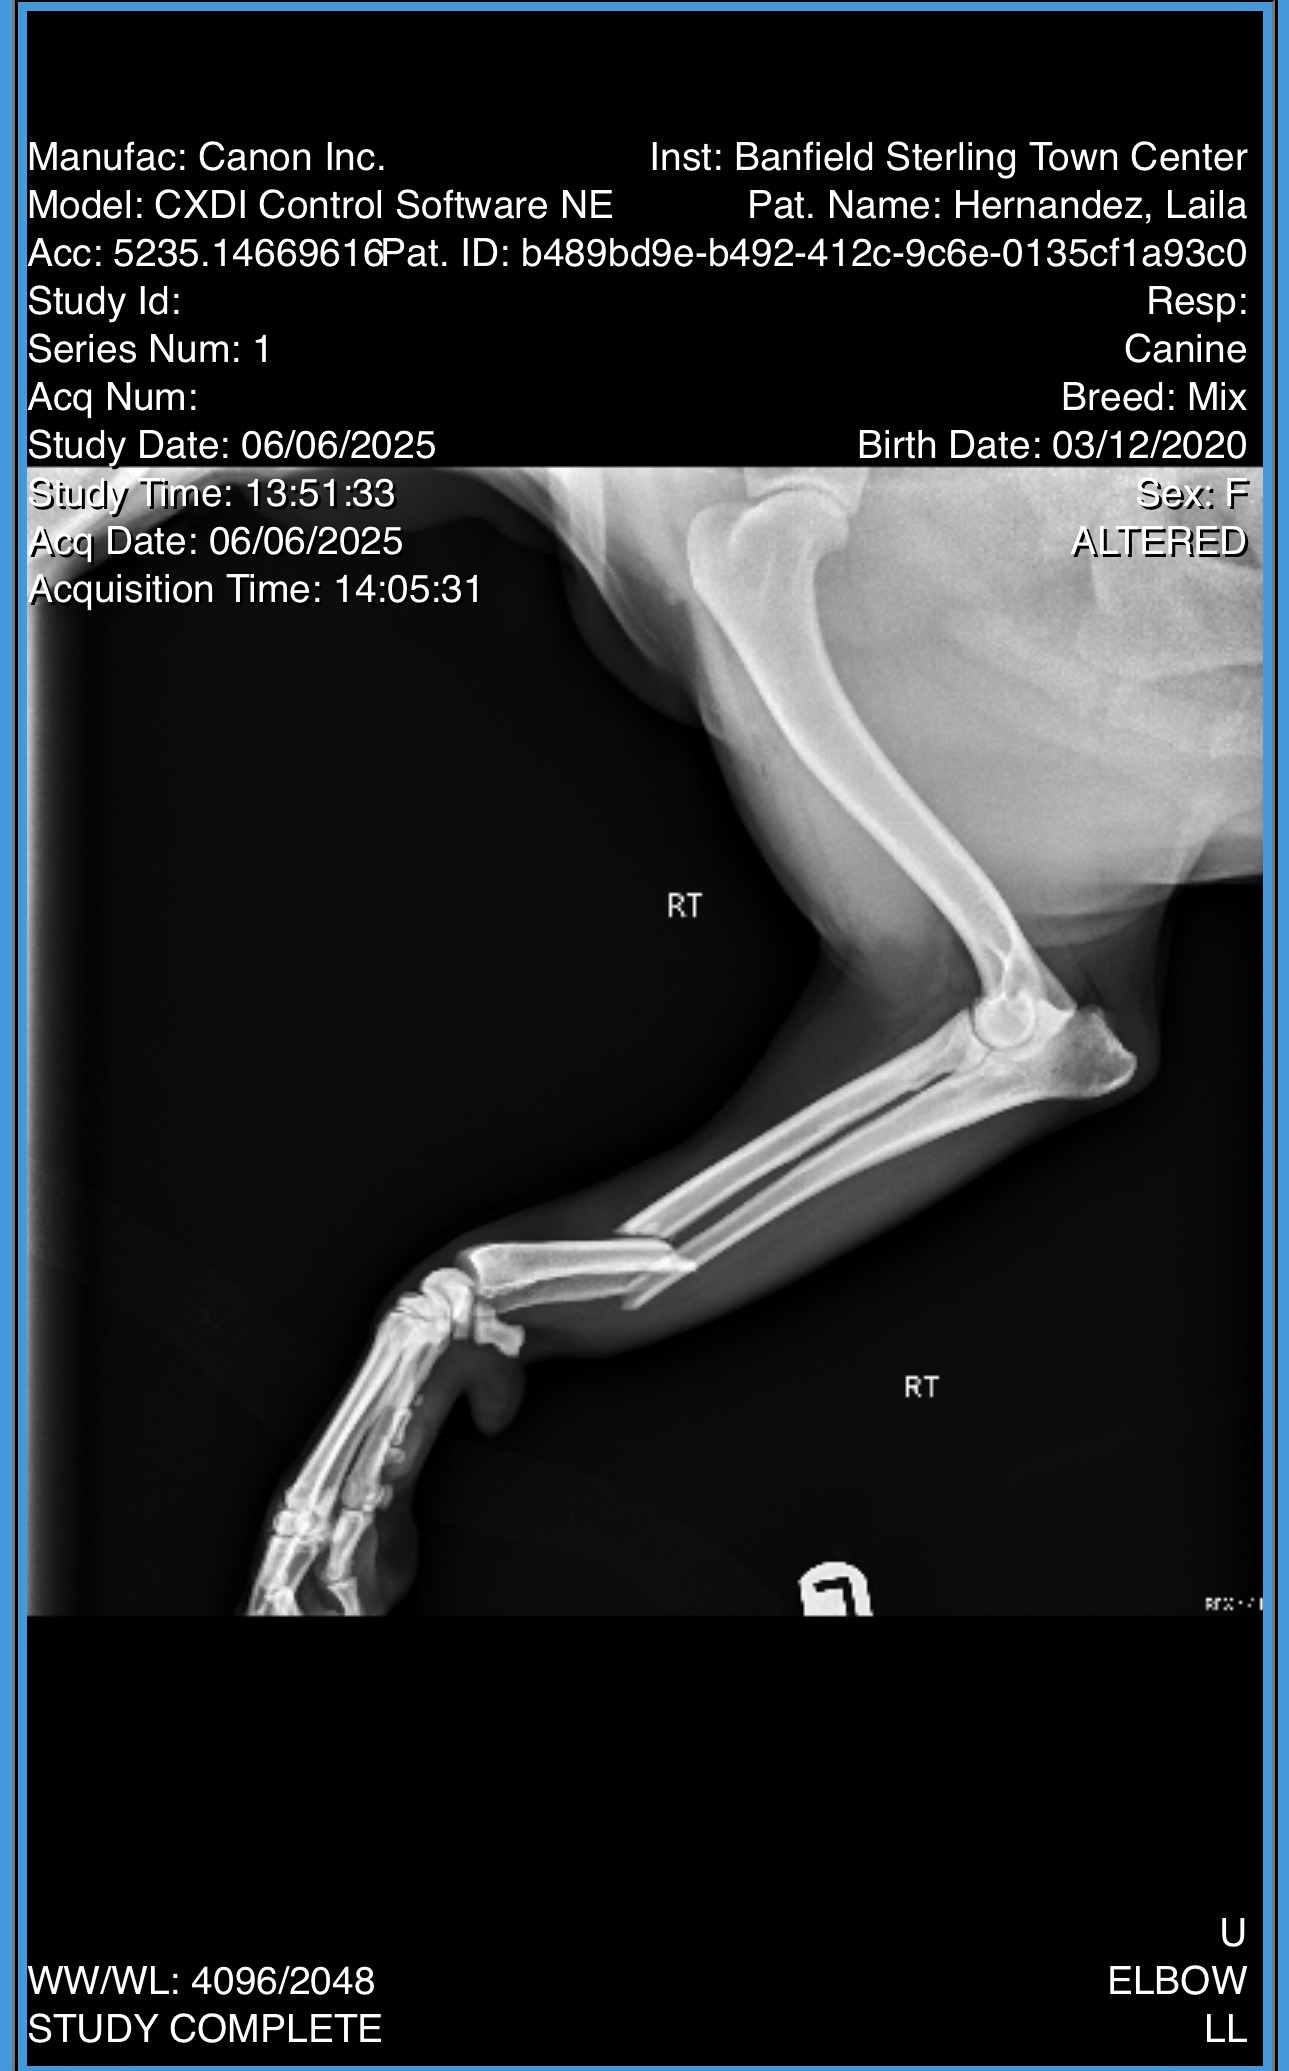

Yesterday, while we were out for a walk, Laila’s playful spirit got the best of her. Trying to chase a squirrel, she collided with a metal pole, breaking her right front leg in two places. The pain and fear in her eyes were heartbreaking. The vet says she needs urgent orthopedic surgery within a week to have the best chance at a full recovery. Right now, she’s on pain medication and immobilized, but that’s only a temporary fix. Without this surgery, her future is uncertain.